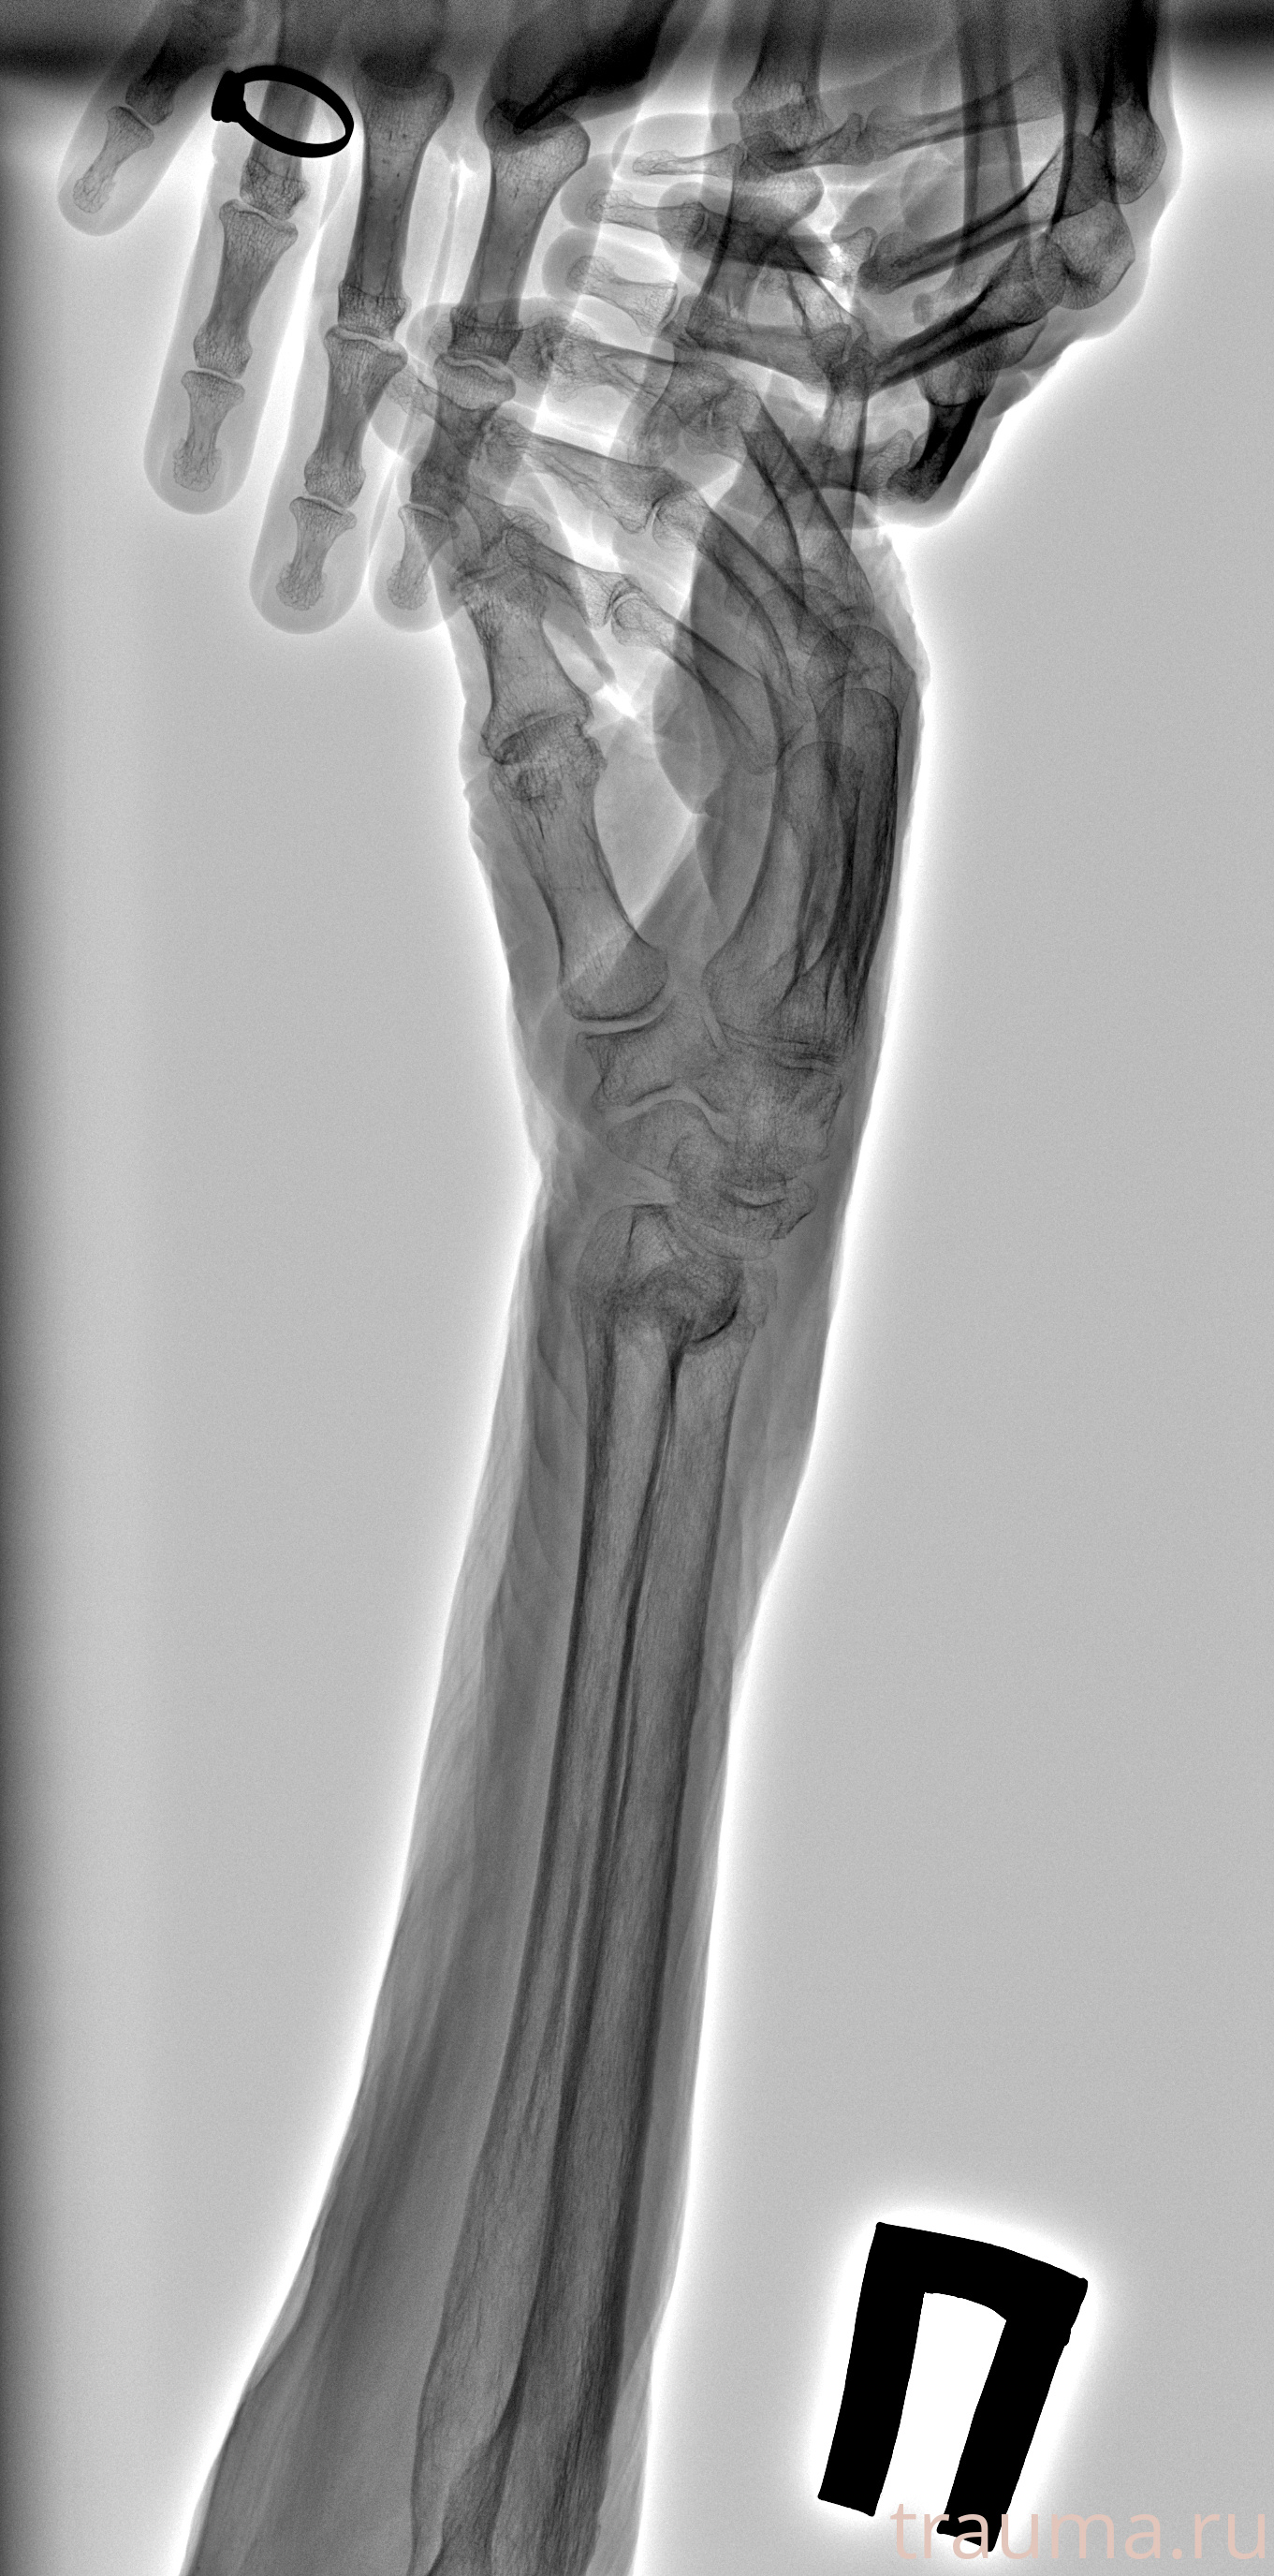

Перелом 3-5 ребер слева

Рентген на дому: по вашему адресу приезжает врач-рентгенолог, травматолог-ортопед с мобильным рентгеновским аппаратом, проводит диагностику травмы или заболевания, делает необходимые рентгенограммы, дает рекомендации по дальнейшему лечению. Получить качественные снимки в домашних условиях возможно благодаря уникальной методике, разработанной МосРентген Центром для института  Склифосовского